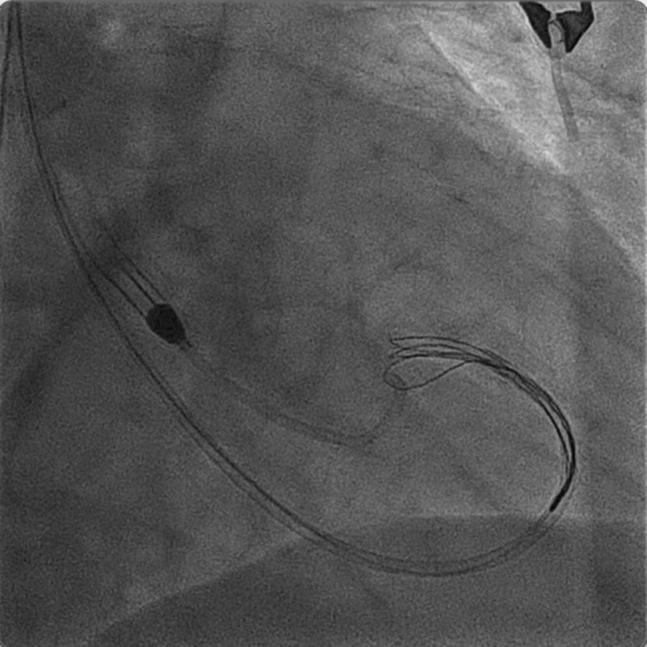

Axial-flow ventricular assist devices are being increasingly used to support hemodynamically compromised patients undergoing percutaneous coronary intervention. Periprocedural valvular complications have been recognized in a few case reports. We present a unique case of entanglement of the Impella within he mitral subvalvular apparatus, retrieved successfully using a snare under fluoroscopic guidance. ().

轴流式心室辅助装置越来越多地用于支持接受经皮冠状动脉介入治疗的血流动力学不稳定患者。少数病例报告中已认识到围手术期瓣膜并发症。我们报告了一例独特的病例,即Impella装置缠绕在二尖瓣瓣下结构内,在透视引导下使用圈套器成功取出。()